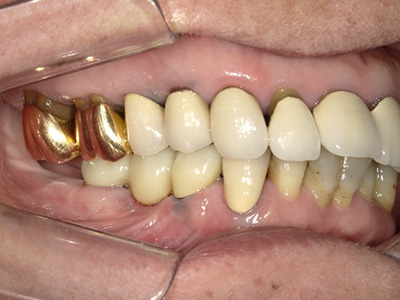

複数の歯がない場合には、

オールオン4、

インプラント

オーバーデンチャーを

検討します

オールオン4

上顎または下顎すべてを4本または6本のインプラントで固定する治療法です。顎の骨が少ない方でも手術可能で、インプラントでしっかりと固定できるためずれたり、外れたりすることが無く噛むことができます。治療費や身体への負担が少ないというメリットがあります。

オーバーデンチャー片顎に2~6本のインプラントを埋入し、アタッチメントを取り付けて入れ歯を固定します。インプラントが固定源となるため、通常の入れ歯よりも安定し、「噛みやすい・フィットする・痛くない」を実現します。すべての歯にインプラントを埋入するよりも、身体的・経済的負担が少ないのも特長です。